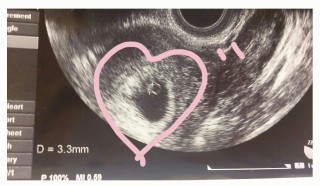

卵黄嚢、胎芽、心拍の確認が出来ました!心拍見えるかな?と先生に言われ見てみるとピコピコ動いていて安心しました。胎芽の大きさは3.3mmでした。